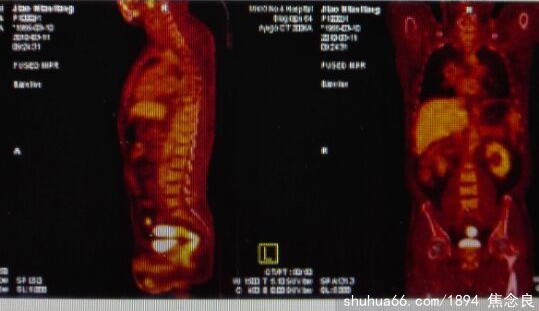

焦念良是红军后代、武术世家、书香门第、受族辈熏陶、自幼习文练武、研习书画、至今笔耕不断、卓有成效。学生时代就是出名的三铁冠军(铅球、铁饼、手榴弹)、游泳健将、武术精英。可惜练的是外家功夫、增强了体质、损伤了五脏、外强中干。在2000年的一天凌晨、突然口腔出血、夫人和单位同志急忙送往当地中心医院急诊科。一量血压、大夫吓了一大跳、高血压258,低血压146,立即转入内科检查、结论是脑出血和心肌梗塞,进入重病监护室、此时本人基本昏迷。我苏醒后、黑乎乎的房间只有我和夫人,夫人几乎吓傻了、脑子一片空白、也不知道通知我的家人、呆呆的守着我、因为大夫说、人醒不过来就与世长辞了、醒过来也是奇迹,苍天有眼、我在冥冥中听到我的夫人声声呼唤我、念良醒醒、别扔下我……。我终于摆脱了死神、在夫人、家人、领导、同志的护理下逐渐恢复、我是中心医院首例血压最高、心脑血管同时发病的严重病人、我打破了医生断言:一是醒不过来、二是终身残疾、三是三年内必会复发。因此、出院后、领导照顾我的工作,从内部管理主岗位上退下来、从事内部质量管理副岗位工作、工作重担减轻了80%、并且感到身体不舒服时、即可休息复查。朋友介绍医学周易专家指导我康复和注意事项、终身服药、精神康复、凡是阴气浓重的地方不能进入(医院太平室、大型墓地、亡故灵堂、公安刑讯室、监狱等),有些伤神的场合和时间及饮食必须注意(出殡、大悲大喜、大型聚会、晚宴、夜晚22时---凌晨4时、白酒、油炸肉食、软体海货、武术、爆发力、重体力、憋便、打架斗殴、着急上火、劳累、久坐、切忌戒酒、戒色、戒疲劳、戒激动、戒熬夜、饮食必须要有规律。离家百里必须有专业医生护理、切莫单身睡眠、天天定期服药复查等等)。还有很多事项、越想越没有活头了、消沉低落。突然想到、自幼学习书画、虽然笔耕不断、因工作繁忙、没有静心研究、因此、每天早起写写画画、在办公室也有时间钻研美术和书法。久而久之、沉醉在书画中、忘记了自己是个特除的病人。随着我的作品的不断提升、我的办公室里的来人越来越多、我知道他们都不是因工作而来、是来求作品的、后来、人们由要到求、由求到买、或是拿东西来换作品的、或是请我吃饭的、脑袋发热、没有注意书画养生、出现了我第二次生命的危机、2010年1月份、我感觉浑身乏力、小腹难受、排便出血、经检查怀疑是肠癌、我2月份去了无锡第四肿瘤医院、确诊是乙状结肠隆起型腺癌、并于3月17日做了切除手术、后来听夫人说、给我准备了8袋血、如果输血、恐怕我下不了手术台了。回到家后、我认为医生说的对、最多三年的活头,什么也干不了了。我夫人和朋友们给了我鼓励、我又重新站起来了、继续研究书画、领导也不在安排我具体工作。2012年我遇书画大师前辈指点、开始走出去、加入书画机构、参加书画展赛、接受媒体报道、出书见报、同时、严格按照医嘱调养自己、凡是阴气浓重的地方坚决不能进入,有些伤神的场合和时间及饮食必须注意、终于冲破了癌症复发3年关口、到现在、我已经闯过了癌症5年大关。但是、在今年的复查时、仍然不太乐观、三高症、高血压二百多、低血压一百多、血糖增高。肺部出现节节、随时跟踪检查、就怕转移。心脑血管都不好、还是保养不够。因此、我目前已经皈依道教、出家为道、带发修行,改掉一切不良习惯、一心研究书画。书画是一种艺术品,它可以陶冶情操,它的美触动我的心境,它的意境感染我的灵魂。一是调血气,通经脉:习书作画要有正确的姿势。头部端正,两肩平齐,胸张背直,两脚平放,这样才能提全身之力。写字作画必须集中精力,心正气和,灵活自若地运用手、腕、肘、臂,从而调动全身的气和力。这样,很自然地通融全身血气,身体内气血畅达,五脏和谐,百脉疏通,使体内各部分功能得到调整,使大脑神经兴奋和抑制得到平衡,促进血液循环和新陈代谢,精力自然旺盛。二是静心宁神:书画活动可以使心理达到平衡。作画习书必须用意念控制手中之笔,“用心不杂,乃是入神要路”。绝虑凝神,志趣高雅,便能以“静”制“动”。这样,使人消除紧张变得遇事沉着。陆游有诗曰:“一笑玩笔砚,病体方知轻。”我的体会是:病魔何所惧、书画换新